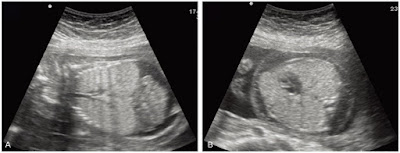

4. Congenital

Diaphragmatic hernia (CDH)

- Abdominal circumference is often small

- Left liver lobe herniates into chest

- Peristalsis of bowel in chest